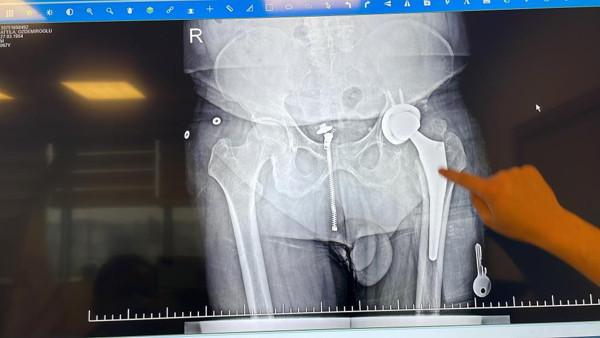

Düzce Atatürk Devlet Hastanesi’nde Ortopedi ve Travmatoloji Uzmanı olarak görev yapan ve uzmanlık eğitimini İstanbul Balta Limanı Kemik Hastalıkları Eğitim ve Araştırma Hastanesi'nde tamamlayan Op. Dr. Ömer Faruk Yılmaz, Attilla Özdemiroğlu’nun ameliyatını çok başarılı bir şekilde gerçekleştirdiklerini belirterek, ameliyatta yapılan çalışmaları anlattı. Yılmaz, "Attilla Özdemiroğlu ile geçtiğimiz sene göreve başladığım zaman tanıştık. Ameliyat ile ilgili düşüncelerimiz vardı. Pandeminin yoğunluğundan dolayı ameliyatını yapamıyorduk. 17 Aralık’ta kalça protezi ameliyatını yaptık. 46 yıl önce kalçasında geçirdiği enfeksiyondan dolayı kendisinde kısalık oluşmuştu. Onun hissettiği 4-5 santim ama röntgende ölçtüğümüz zaman 2.5-3 santimlik bir kısalığı vardı. Biz oradaki çürümüş olan kemiği çıkartarak, ona baş ve bir soket yapıp protez yaptık. Röntgen olarak 3 santimlik bir uzamamız oldu. Ama hastamızın hissettiği 4.5 santime kadar bir uzama var" dedi.